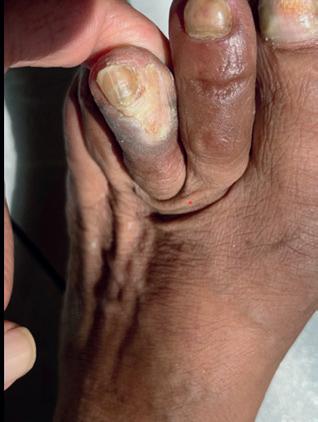

A 78-year-old man who resides in Uzbekistan presented to the office with CLTI of the left lower extremity manifested by a non-healing gangrenous left toe ulcer and associated rest pain (Figure 1). He was initially evaluated by providers in his home country and had a recent arteriogram in Uzbekistan demonstrating severe multi-level arterial disease in the left lower extremity,

The patient had an uneventful postoperative recovery. His post-intervention lower extremity arterial studies demonstrated a significant improvement in both the ABI and toe-brachial index (TBI). At his onemonth postoperative visit, he had completely healed the toe ulcer without any further intervention (Figure 5).